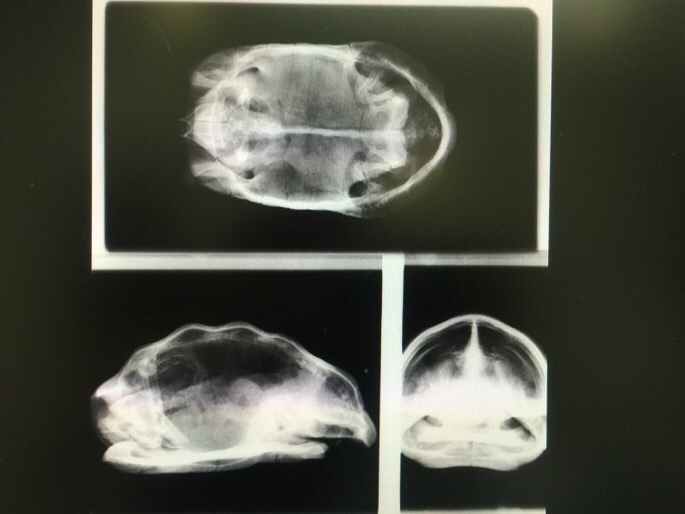

鼻水を出していることから肺炎を疑われたようで、まずはレントゲン撮影。

特に問題なさそうで、腫れが何なのかは分かりませんでした。